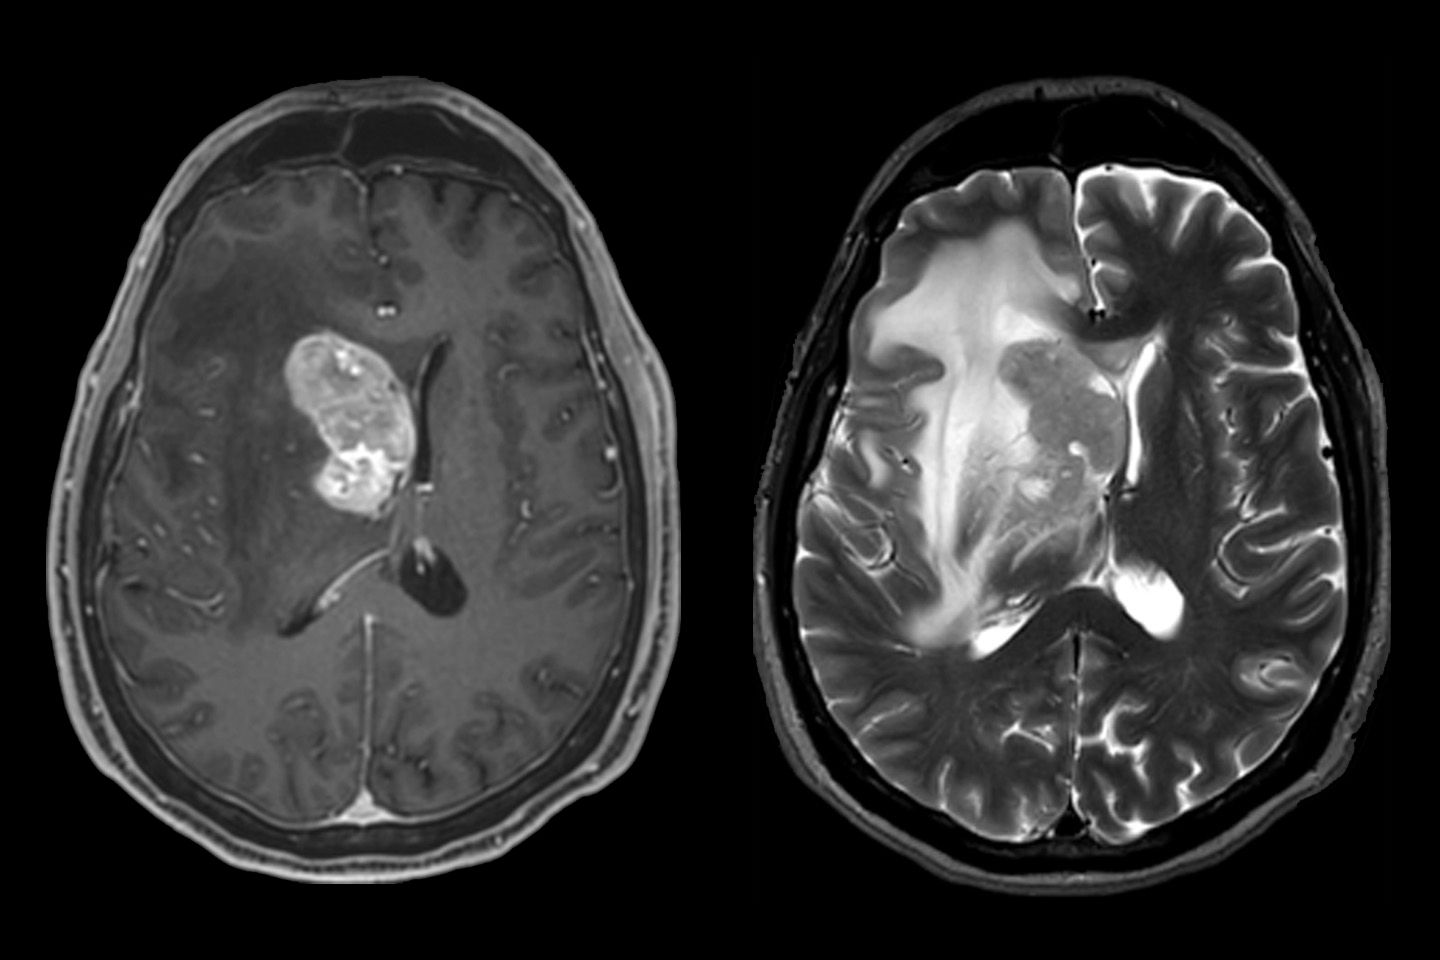

Neuroradiologische Diagnostik eines Gehirntumors mittels Magnetresonanztomographie (MRT)

MRT (Magnetresonanztomographie)

Ohne Strahlung werden mit Hilfe eines starken Magnetfeldes detaillierte Bilder (sogenannte Sequenzen) von Gehirn, Rückenmark, Nerven, Weichteilen und Knochen erstellt.